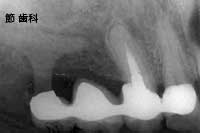

① この写真は平成5年に、治療完了後の状態の確認のために撮影したもので、治療はその前年に行われています。簡単に説明すると、歯の残存状態が上顎は大臼歯(奥歯)3本のみ残して11本が失われ、下顎がその逆に大臼歯全てと右下の犬歯とその後ろも含めて合計6本が失われ、上下で互い違いの関係の、すれ違い状態になっていました。

上顎は大臼歯3本が比較的しっかりとしていたので、それを支えとしたシリンダータイプ(コーヌス)義歯にて全歯を、下顎は両側の大臼歯部に、当時良く使われていた“人工サファイヤ”のU字型をしたタイプと、右下犬歯部にはチタンコートのブレード型POIインプラントを採用し、隣在歯と連結することで欠損補綴を行い、崩壊した状態の口腔内と、失われてしまった状態の咬み合わせの再建を図ったものです。